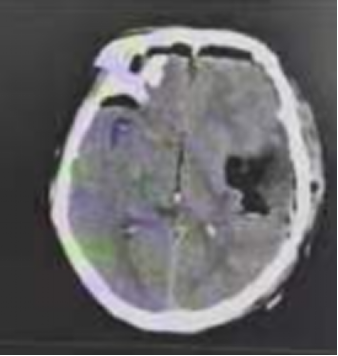

术前MRI

65岁的李大爷(化名)因“右侧面瘫伴有右侧上肢活动不灵、言语不利2周”来我院就诊,李大爷自述,觉得近期出现右侧面瘫伴有右侧上肢活动不灵、言语不利,且症状进行加重,经多方打听慕名来西安交大一附院榆林医院神经外科二病区找到纪文军主任医师。来院后,行头颅MRI检查提示:左侧额顶叶占位,考虑为胶质瘤。